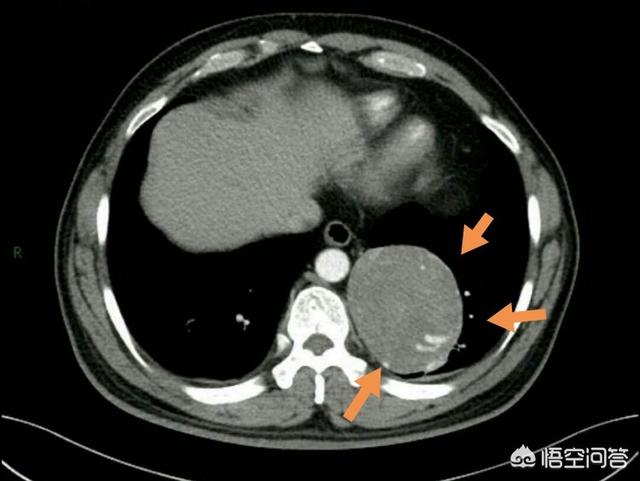

Il existe de nombreuses tumeurs bénignes dans l'ensemble du corps, telles que le chondrosarcome et le fibrome non ossifiant des os, les tumeurs malignes des poumons, le pneumocytome sclérosant, l'ostéome des sinus, les méningiomes relativement petits, les angiomyolipomes rénaux et les lipomes sous-cutanés, etc., et tant qu'elles n'affectent pas la fonction des organes et qu'elles n'évoluent pas rapidement lors des observations de suivi, il n'est pas nécessaire de les opérer.

À l'inverse, certaines tumeurs bénignes ont un potentiel malin et peuvent devenir cancéreuses à l'avenir, ou bien la tumeur est relativement importante et interfère avec le fonctionnement de l'organe, ce qui nécessite une ablation chirurgicale.

Il s'agit par exemple d'ostéochondromes de taille relativement importante, de pneumocytomes sclérosants, de tumeurs osseuses à cellules géantes et de tumeurs bénignes qui provoquent une obstruction du tractus gastro-intestinal.